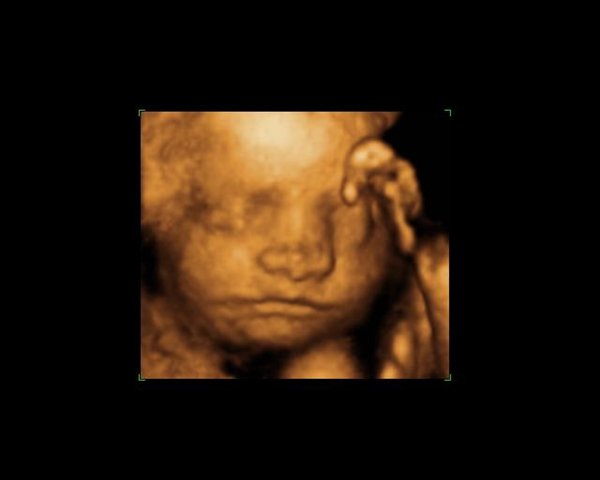

jeg tror ikke barnet er for stort efter uge 30, men det kommer måske an på hvor stor barnet er. Da jeg blev 3D/4D scannet vejede den lille ca. 1761 gram, mit lille problem var bare at vores bebse lå med hovedet godt ned allerede, så hun var nød til at scanne mig imens jeg lå på siden, for lige at få ansigtet frem

Men vi fik fine billeder med hjem